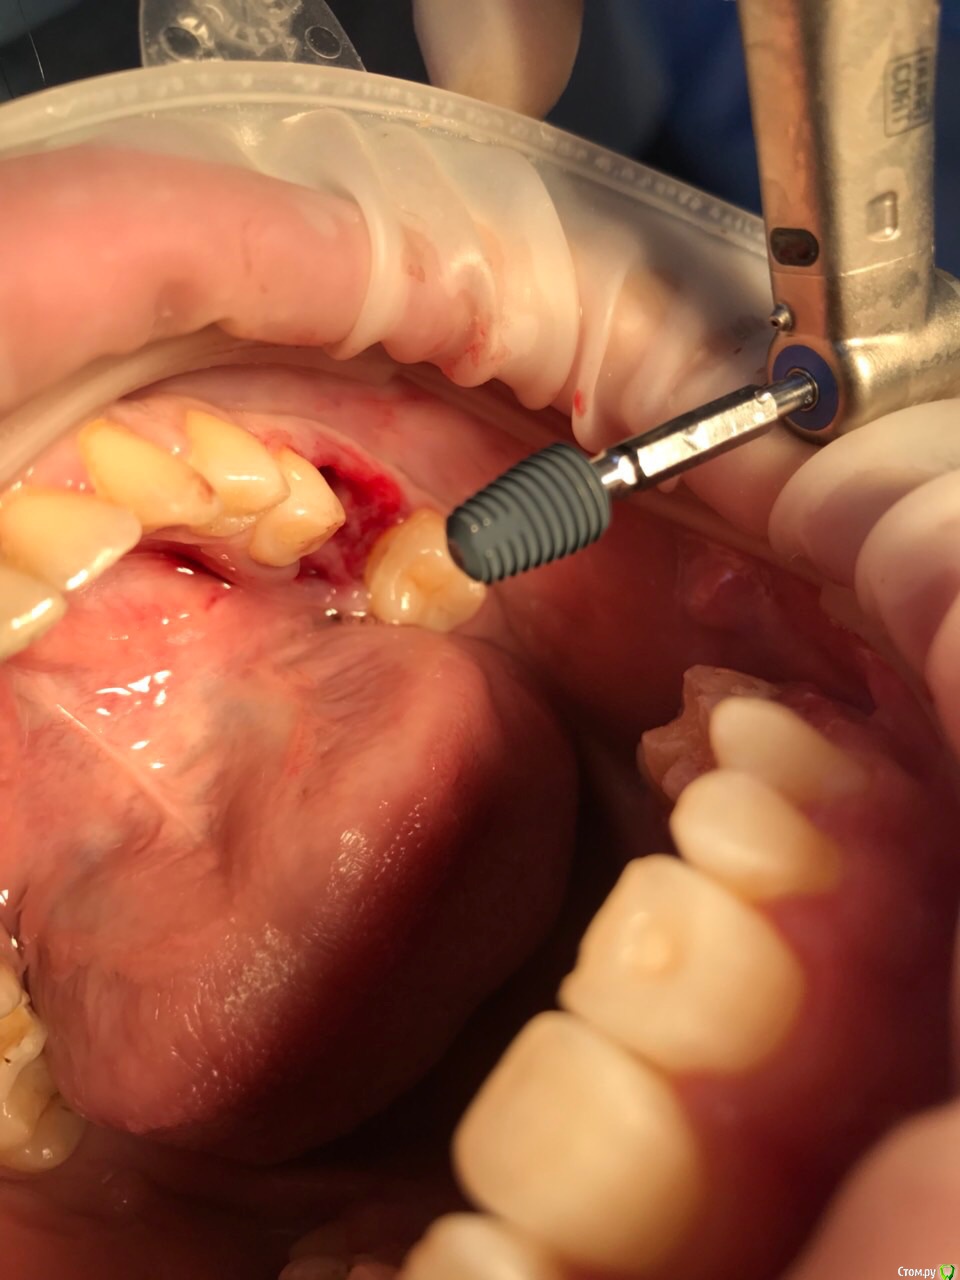

dr.Dre Опубликовано 14 июля, 2018 Поделиться Опубликовано 14 июля, 2018 Добрый вечер,коллеги такая ситуация разработал лунку под имплант , 2-3 витка при установке не доходит, пркручиваеться, извлёк имплант засверлился глубже тоже самое, в чем причина незнаю.Импланты megagen,icx active Ссылка на комментарий

dr.Dre Опубликовано 15 июля, 2018 Автор Поделиться Опубликовано 15 июля, 2018 Камрад, а челюсь то какая и картику имплантата покажи, че за зверь?нижня челюсть , megagen 6,0 Ссылка на комментарий

Irouil Опубликовано 15 июля, 2018 Поделиться Опубликовано 15 июля, 2018 Если отвечать по теме - я думаю, Вы не попадаете верхушкой в костное ложе. В лунках однокоренных зубов обработка происходит либо за ее пределами в апикальном направлении, либо в оральной стенке. Если Вы сверлились в стенку, то имплантат может проскакивать вход в ложе, т.к. ради торка Вы, вероятно, не до конца следуете протоколу. Я не работал с мегадженом, но с астрой у меня бывает такая проблема - верхушка тупая, широкая и проваливается в лунку. Так как я кручу наконечником (и я пробовал пару раз ключём, это просто ппц), то скачка не происходит - просто имплантат елозит по стенке, пока не упирается в дно лунки. Если лунка узкая - можно даже торк получить!) Если все так, то советы следующие: по протоколу доработать хотя бы первый мм костного ложа; начинать вводить имплантат под сильным углом с направлением в оральную стенку, потом выправлять его наклон. Ссылка на комментарий

dok1 Опубликовано 15 июля, 2018 Поделиться Опубликовано 15 июля, 2018 С этого и надо было начинать. Фрезой тут сложно будет выпрямить по оси. Очень аккуратно сносить все выступы в лунке. Ссылка на комментарий